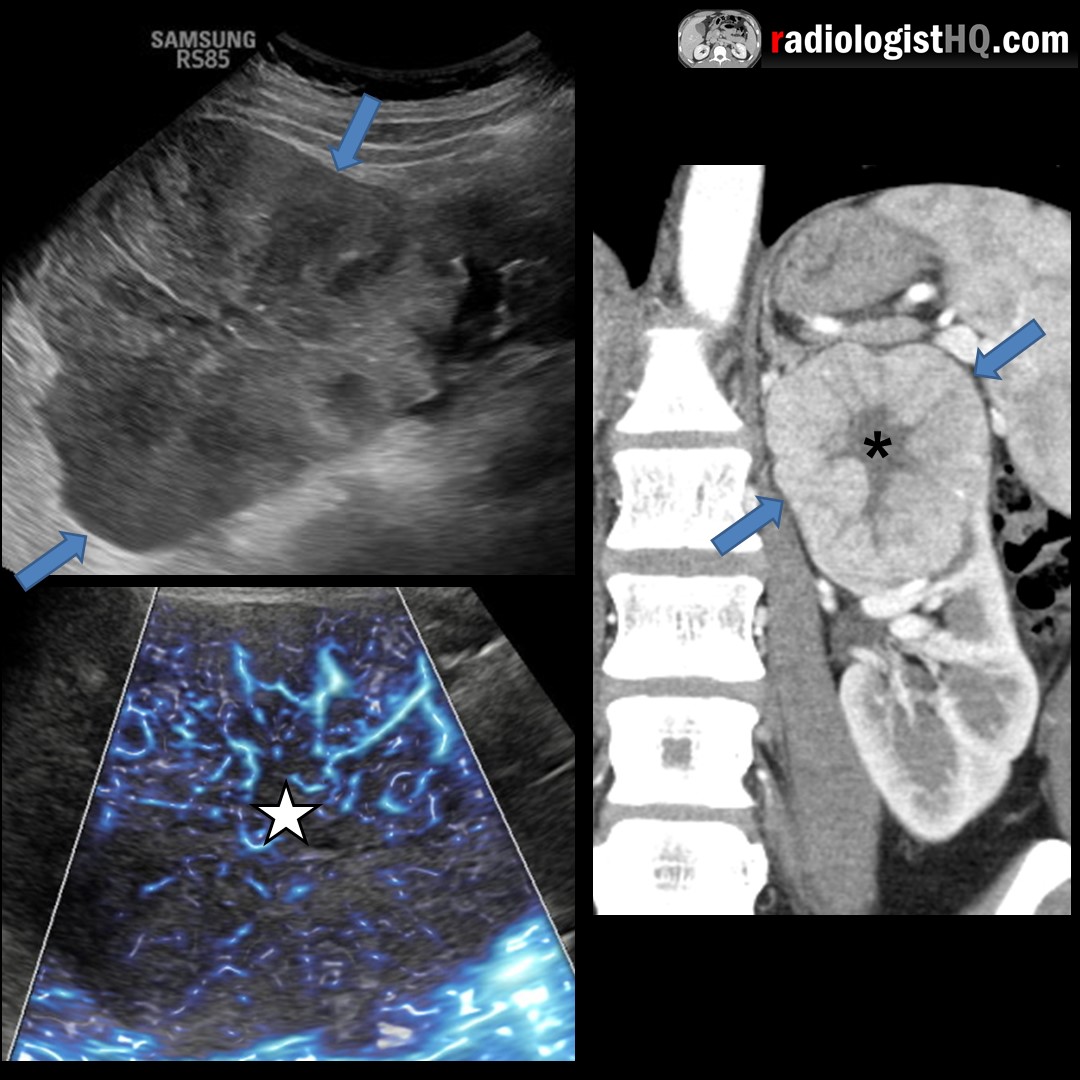

Ultrasound & CT of Renal Oncocytoma r/Radiology Spoke Wheel Enhancement Radiology Meningiomas can have a dual blood supply. The majority of tumors are predominantly supplied by meningeal vessels; Spoke Wheel Enhancement Radiology.

spokewheel NephroPOCUS Spoke Wheel Enhancement Radiology Meningiomas can have a dual blood supply. The majority of tumors are predominantly supplied by meningeal vessels; Spoke Wheel Enhancement Radiology.

Typical Imaging Findings of Renal Oncocytoma Spoke Wheel Enhancement Radiology Meningiomas can have a dual blood supply. The majority of tumors are predominantly supplied by meningeal vessels; Spoke Wheel Enhancement Radiology.

Oncocytoma Spoke Wheel Enhancement Radiology The majority of tumors are predominantly supplied by meningeal vessels; Meningiomas can have a dual blood supply. Spoke Wheel Enhancement Radiology.